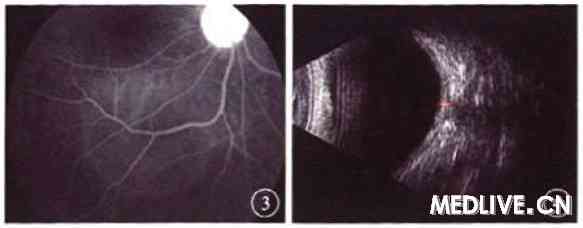

FFA检查:右眼早期后极部片状弱荧光,静脉期视盘颞侧点状强荧光,晚期少量荧光渗漏,视盘晚期强荧光,颞下方可见约2.0 DD×2.0 DD的局限性渗出性视网膜浅脱离(图3);左眼未见异常荧光。

图3 第3次就诊时患者右眼FFA像,视盘颞下方局限性渗透性视网膜浅脱离,视盘晚期强荧光

本例患者第3次就诊于我院时,右眼眼痛、视力下降,眼底检查可见局限性渗出性视网膜脱离;FFA检查显示,早期点状强荧光,晚期荧光渗漏;B型超声检查显示,右眼眼球壁弥漫性增厚,球壁外侧有一无回声区,可见“T”型。口服糖皮质激素治疗后,症状体征明显改眷,可明确右眼后巩膜炎的诊断。